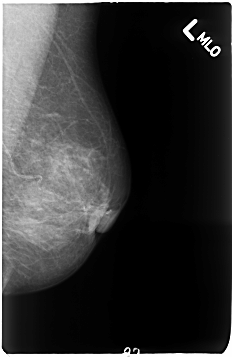

B_3050_1.LEFT_MLO

LEFT_MLO LINES 4632 PIXELS_PER_LINE 3008 BITS_PER_PIXEL 12 RESOLUTION 50 NON_OVERLAY